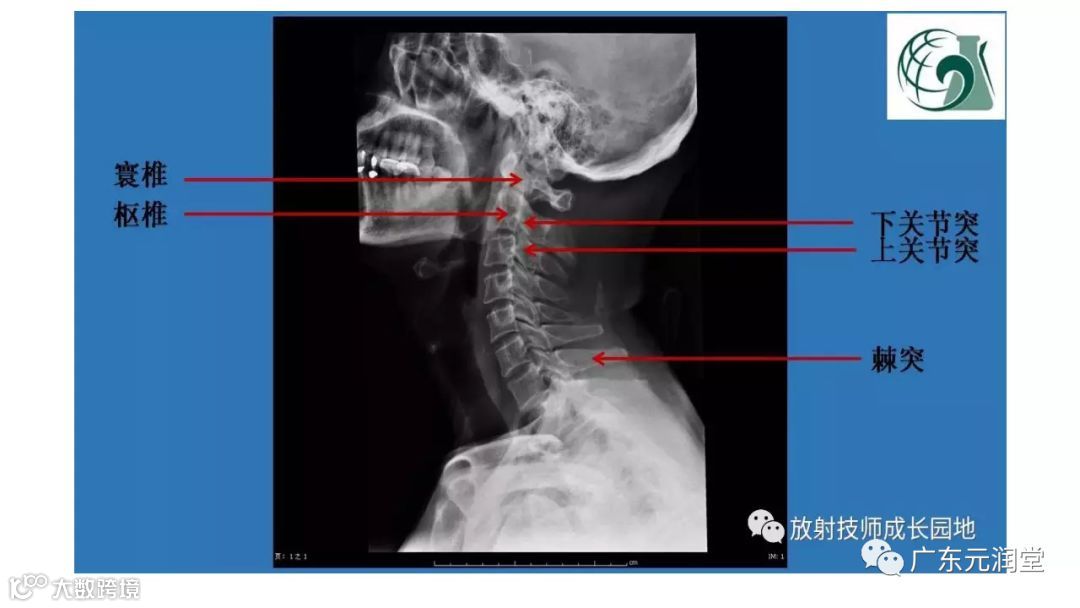

全身常见骨折X线汇总

来源丨

新乡

医学影像